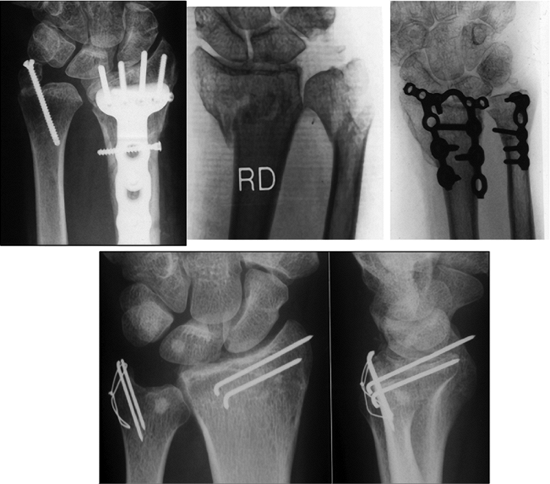

Figure 13.4.

Implants constructed specifically for the anatomy of the distal radius have allowed limited fixation of fracture components and minimization of prior problems associated with larger nonspecific implants. |

wire forms (Figs. 13.19 and 13.20).